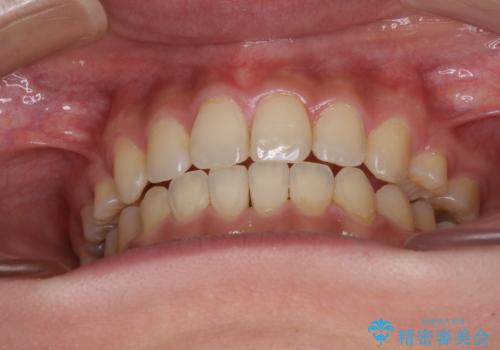

- 前歯のオープンバイトを気にして来院された患者様です。

上下前歯の前後位置が大きくずれていたため、上顎左右第一小臼歯2本を抜歯してワイヤー装置による矯正治療を行うこととしました。

オープンバイトの原因は舌の突出癖であり、癖が改善されないと治療経過に影響を及ぼすため、舌のトレーニングを指示しました。

なかなか癖が改善されず、トレーニングも断続的に行ったため、治療期間は長期化しました。